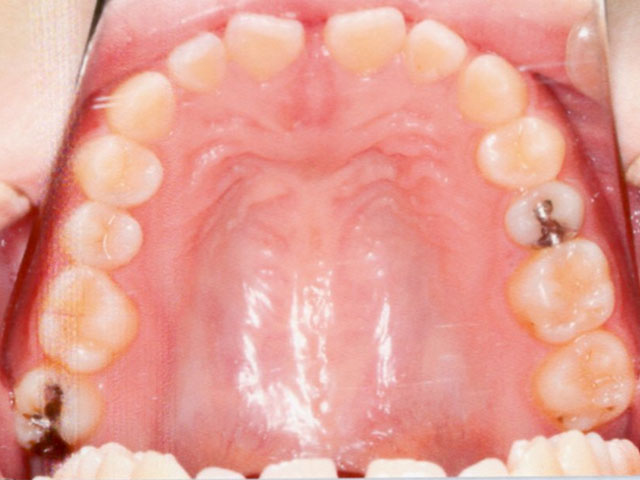

症例02【空隙歯列】

16歳9か月(男子)

上下の顎の成長・発育のバランスには問題はなく、骨格的な不調和は認められませんでした。

ただし、歯の大きさが平均よりもやや小さいことに加え、舌で前歯を押し出す癖(舌突出癖)がみられ、これが前歯の位置に影響している状態でした。

そのため、治療計画は非抜歯とし、スタンダードエッジワイズ法による矯正治療を選択。

同時に、舌突出癖を改善するためのトレーニングも併せて行いました。

治療期間は1年11か月で、その後は保定へ移行。